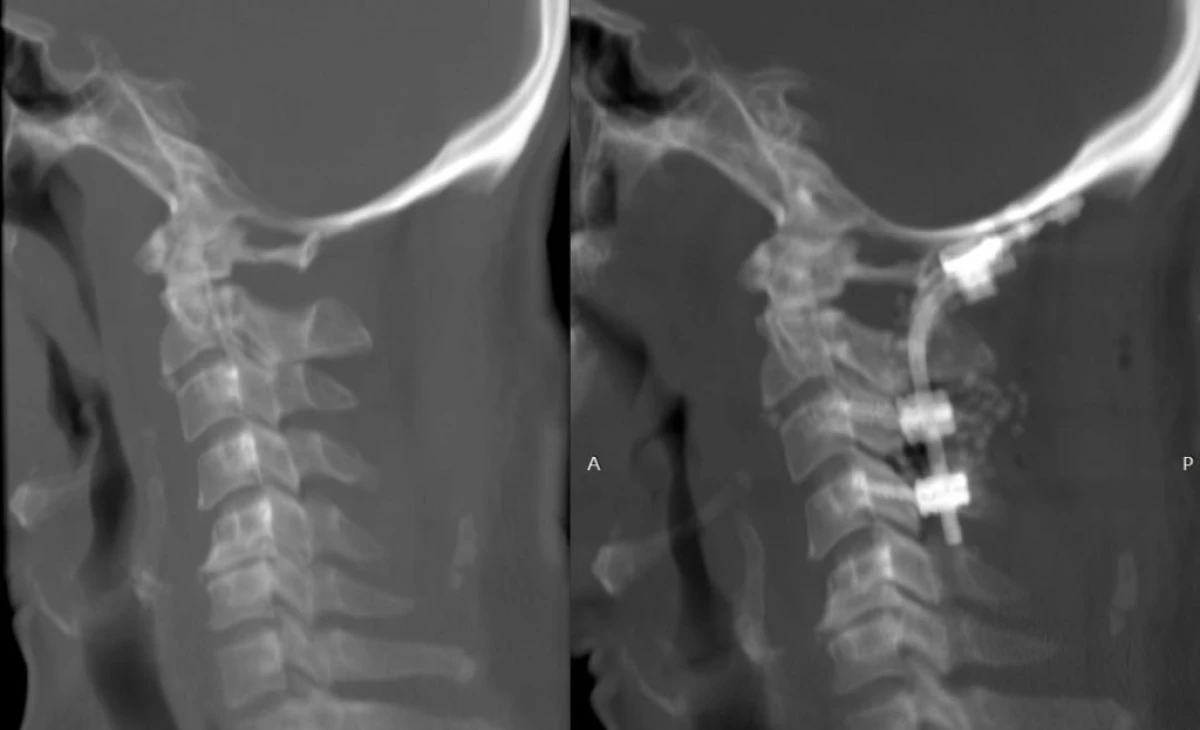

އައިޖީއެމްއެޗްގައި ހެދި އޮކްސިޕިޓޯ-ސަރވިކަލް ފިއުޝަން ސާޖަރީގެ ތެރެއިން، ފޮޓޯ: އައިޖީއެމްއެޗް

ފުރަތަމަ ފަހަރަށް އައިޖީއެމްއެޗްގައި އޮކްސިޕިޓޯ-ސަރވިކަލް ފިއުޝަން ސާޖަރީއެއް ހަދައިފި

އެންޑޯސްކޮޕިކް ސަޕައން ސާޖަރީ ނުވަތަ މައިބަދައަށް ކެމެރާ ލައްވައިގެން ހަދާ ސާޖަރީއެއް ފުރަތަމަ ފަހަރަށް ރާއްޖޭގައި އިންދިރާ ގާންދީ މެމޯރިއަލް ހޮސްޕިޓަލް (އައިޖީއެމްއެޗް)ގައި ކާމިޔާބުކަމާއެކު ހަދައިފިއެވެ.

އައިޖީއެމްއެޗްގެ ނިއުރޯ ސާޖަރީ ޑިޕާޓުމެންޓުން ހެދި މި ސާޖަރަީއަކީ މައިބަދައިގެ ޑިސްކު ސްލިޕުވުމާއި، ނާރު ފިތުމާއި އެނޫންވެސް އެކި މައްސަލަތަކާ ހުރެ ބުރަކަށީގައި ރިއްސާ ރިހުންތަކަށް ފަރުވާދިނުމަށް ހަދާ ސާޖަރީއެކެވެ.